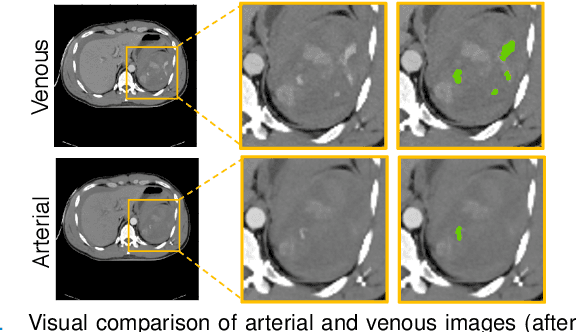

Abstract:The spleen is one of the most commonly injured solid organs in blunt abdominal trauma. The development of automatic segmentation systems from multi-phase CT for splenic vascular injury can augment severity grading for improving clinical decision support and outcome prediction. However, accurate segmentation of splenic vascular injury is challenging for the following reasons: 1) Splenic vascular injury can be highly variant in shape, texture, size, and overall appearance; and 2) Data acquisition is a complex and expensive procedure that requires intensive efforts from both data scientists and radiologists, which makes large-scale well-annotated datasets hard to acquire in general. In light of these challenges, we hereby design a novel framework for multi-phase splenic vascular injury segmentation, especially with limited data. On the one hand, we propose to leverage external data to mine pseudo splenic masks as the spatial attention, dubbed external attention, for guiding the segmentation of splenic vascular injury. On the other hand, we develop a synthetic phase augmentation module, which builds upon generative adversarial networks, for populating the internal data by fully leveraging the relation between different phases. By jointly enforcing external attention and populating internal data representation during training, our proposed method outperforms other competing methods and substantially improves the popular DeepLab-v3+ baseline by more than 7% in terms of average DSC, which confirms its effectiveness.